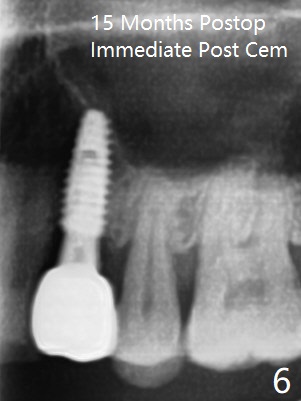

In fact the designed initial drills do not get to the bone with guides. After use of the next length drills (1.5 mm longer with sharp end), the sinus floor perforates without membrane perforation. Once 3.5 mm drill is used following sequential osteotomy, a 4x10 mm dummy implant is placed for sinus lift with 1 mm short of the depth and >50 Ncm. Following the dummy implant removal, allograft in the amount of 2 to 3 amalgam carriers is delivered for sinus lift (Fig.1,2 white *), followed by implant placement (4.5x10 mm, >55 Ncm). More allograft is placed before and after abutment insertion (black *). As usual, an immediate provisional is fabricated at each site. After removal and cleaning, the abutments are reseated and retorqued to 30 Ncm 11 months postop (Fig.3,4). Sinus lift is indistinct 15 months postop (Fig.5,6), probably due to radiation overexposure, although placement trajectory is good.